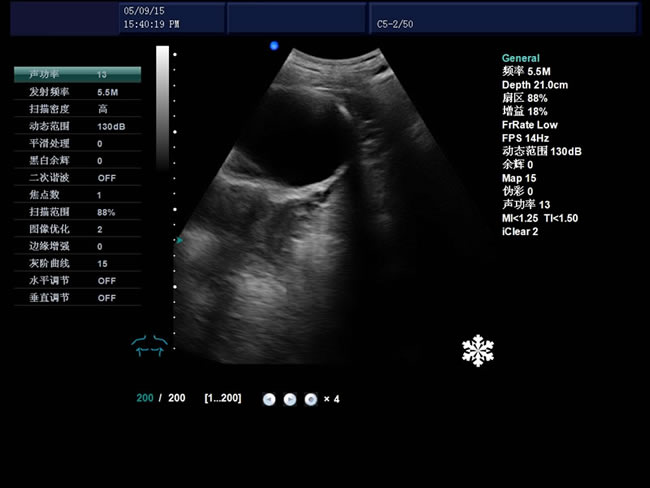

S8 彩色多普勒獸用超聲診斷儀

• S8彩色多普勒獸用超聲診斷儀是徐州市大為電子設備有限公司推出的一款全新的彩色超聲診斷儀器。

電影回放存儲